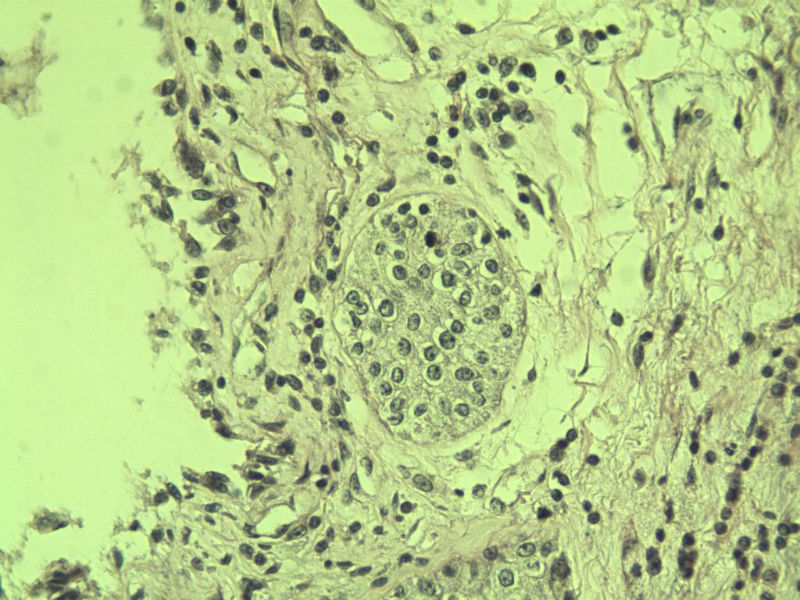

男 75岁 因排尿困难半年行前列腺切除术,体积 4 × 3 × 2.5 cm3,切面灰白,实性,质韧。请各位老师看看 有问题没? 谢谢了!

良性前列腺增生伴尿路上皮化生

呈巢上皮为尿道周围前列腺组织正常现象。尿路上皮-前列腺腺体过度。

前列腺增生症伴鳞化

前列腺增生伴尿路上皮鳞化及Brown巢形成,未见恶性。